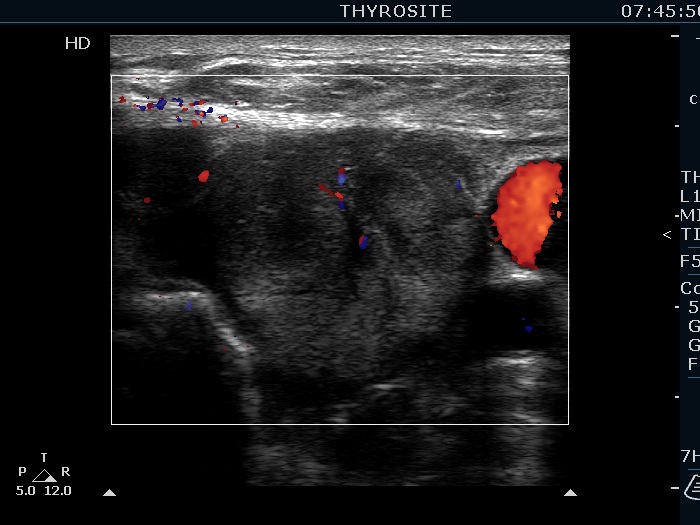

Ultrasonography. The right lobe was echonormal and presented several hypoechoic nodules. A large, inhomogeneous, partly deeply hypoechoic, partly minimally hypoechoic or echonormal mass occupied the left lobe. The borders of the tumor were irregular. There were multiple lymph nodules upper and lateral to the left thyroid lobe. The nodes had a heterogeneous pattern and lacked hilum. The vascularity was scanty both in the thyroid nodules and the lymph nodes.